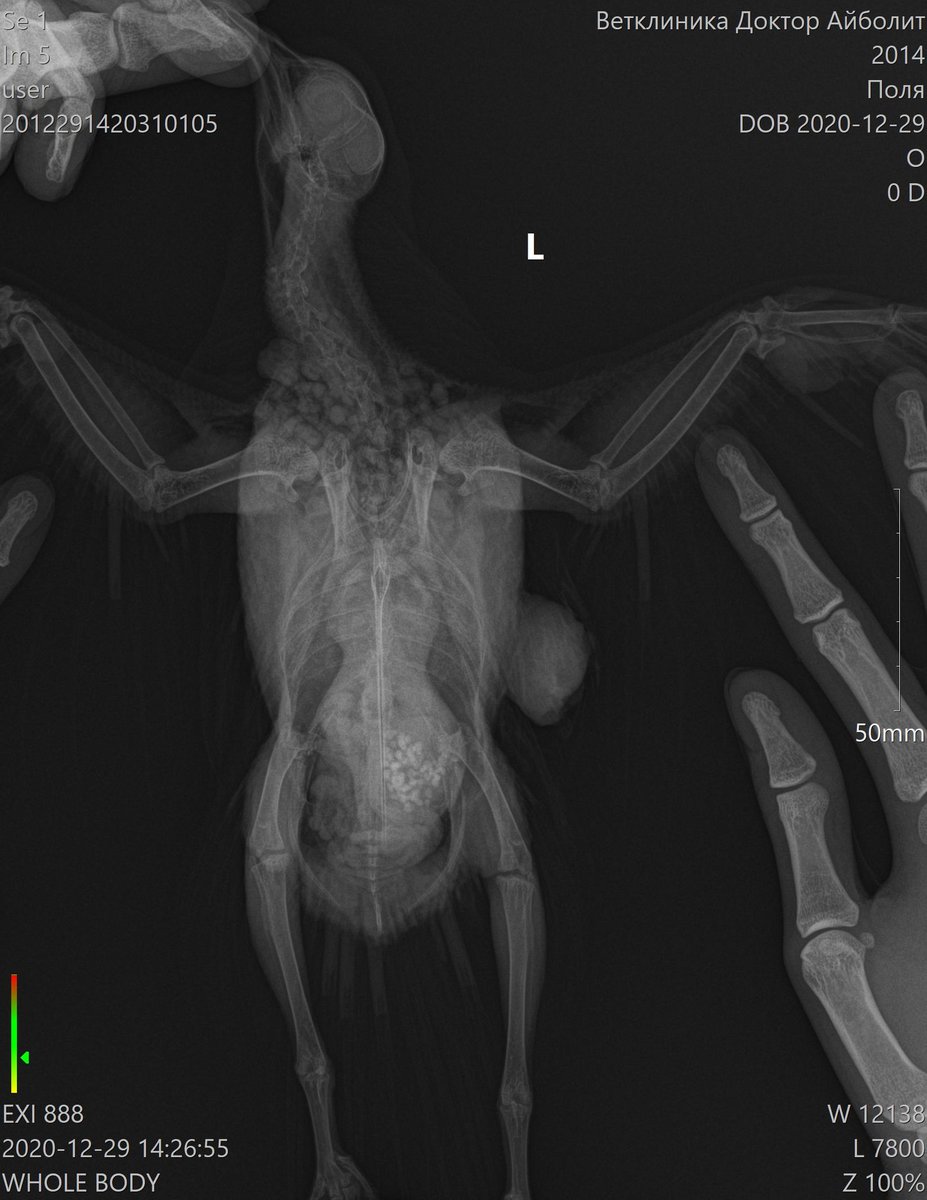

Lia V Опубликовано 30 декабря, 2020 Автор #25 Опубликовано 30 декабря, 2020 Добрый вечер, как обещала, рассказываю о результатах похода к хирургу. Вчера сделали операцию моему красавцу. Он, мягко говоря был сильно удивлен, сказал, что ранее такого не встречал. Приложу фото, которое он сделал во время операции. Этих шишек было 2, размеры и скорость роста шокируют (((((((((( одну хорошо видно на рентгене, вторая была на крыле (на плече, она была меньше, скрыта в перьях и не так заметна, на фото именно она). Природа этих наростов не ясна((((( Гистология будет готова только через 21 день. Назначили пить амоксиклав, флуконазол, гепатовет, кальция глюконат, транексам, ветом. Завтра записалась на контрольный повторный прием к орнитологу. Попрошу ее дотошно его с ног до ушей осмотреть (у меня это получается плохо, он вертится, я все время боюсь, что швы разойдутся и не рискую его сильно крутить. У врача, естественно, это получается ловко и умело). По цене операция + 2 проекции рентгенографии и гистология вышли в 7.300 руб. Сидит мой Поля с собранным крылом, в воротнике, летать не пускаю, гуляет только по клетке. Скучно ему. От избытка энергии чистится как дурной (ему больше реально и делать нечего), воротник спасает лишь частично, я все переживаю как бы не расковырял раны. Честно говоря, у меня паника и ощущение полой неопределенности. Спасибо врачам огромное, но ситуация все равно пока не ясная совершенно. Встречалась ли Вам такая ситуация??? Что это может быть???

Zosia Опубликовано 30 декабря, 2020 #26 Опубликовано 30 декабря, 2020 Меланома или меланоцитома. Встречались, конечно... Кроме всего прочего у птицы гипертрофия сердечной мышцы, дилатированное сердце. Есть так же некие объекты по верхней границы печени (в ВД проекции) и справа (для смотрящего на снимок- слева) https://public.fotki.com/Shemlik/cancer/operacia001.html https://public.fotki.com/Shemlik/cancer/55.html https://public.fotki.com/Shemlik/cancer/59.html#media https://public.fotki.com/Shemlik/cancer/05-09-20-002.html https://public.fotki.com/Shemlik/cancer/05-09-20-001.html#media